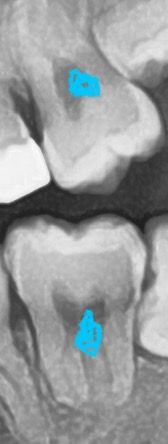

교합면 레진급 충치 파노라마에 잘 보이나요?

파노라마에 아무것도 안보여요 원래 교합면 레진정도의 충치는

파노라마안에 잘 안 보이나요? 구강검진이 더 잘보이나요?

• 1번 째 사진

파노라마 상에서도 관찰 됩니다. 구강 검진에서 보이고 파노라마에서 안보일 수도 있습니다.

치근단 사진이 가장 정확합니다.

교합면에 잇는 간단한 충치는 엑스레이 상으로 확인이 안되는경우가 많습니다 엑스레이 상에서 보이는경우는 충치가 상당히 진행된경우라고 생각하시면됩니다.

파노라마는 치아를 2차원 쪽으로 보는 데다 해상도에 한계가 있기 때문에 작은 충치를 보기 힘듭니다.

작은 충치는 육안으로 확인해야 보이는 경우도 있으니 치과에서 검진을 받아 보는 것이 충치의 유무를 파악하는데 더 정확합니다.

교합면 충치는 시진(직접 보는것)이 중요하고, 방사선 사진은 어느정도의 깊이로 충치가 있는지 참고용입니다.